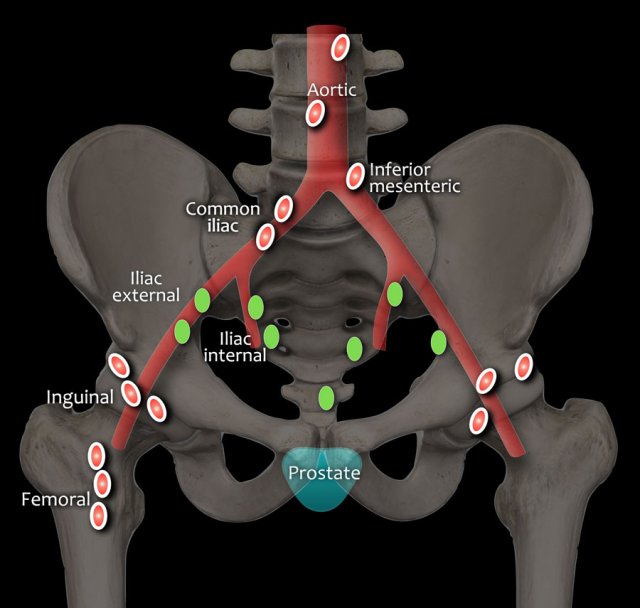

N-stage

DWI is the best sequence for detection of lymph nodes.

T1W series are useful for interpretation of the border contour and signal characteristics of lymph nodes.

MR has a low accuracy for distinguishing positive or negative lymph nodes if characterization is based on size alone.

The following characteristics are considered suspicious:

- round shape and short axis of ≥8mm

- oval shape and short axis of ≥10mm

- heterogeneous appearance

- irregular margins

Regional lymph nodes (green) are below the level of the common iliac junction and are staged N1:

- pelvic

- hypogastric

- sacral

- iliac (internal, external)

Distant lymph nodes (red) are outside these regions and are staged as metastatic disease M1a:

- aortic

- common iliac

- inguinal

- supraclavicular